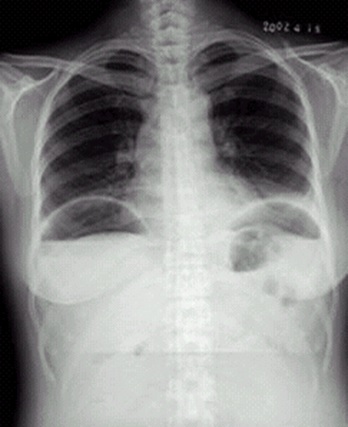

04卷-4.病史:女性,42岁,腹痛1天,进行性加重。诊断(本题满分2.00分)

D.消化道穿孔

本题答案:D

题目解析:【该题针对“X线-消化道穿孔”知识点进行考核】